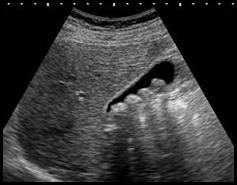

Zamieszczone na ilustracji obrazy dotyczą badania

A. dopplerowskiego.

B. audiometrycznego.

C. scyntygraficznego.

D. densytometrycznego.